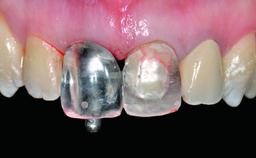

Prosthesis Type FDP

SAC Level Advanced

Defining Characteristics One missing tooth to be replaced by an implant-borne crown

Loading Protocol Conventional or early

Retention Screw-retained Screw-retained

Provisional Implant-Supported Prosthesis Prosthodontic margin > 3 mm apical to mucosal margin Prosthodontic margin > 3 mm apical to mucosal margin

Interim Prosthesis during Healing Fixed Fixed